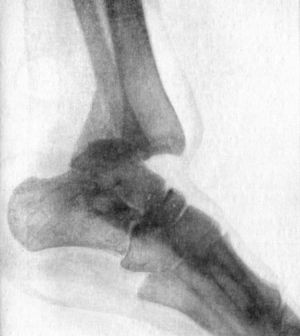

186 94.Radiogram of Pott's Fracture, with Lateral Displacement of Foot

187 95.Ambulant Splint of Plaster of Paris